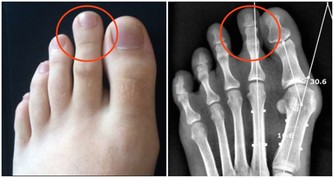

不僅是兩手如此,也要以相應要領每天揉揉雙腳。要養成揉揉手、捏捏腳的習慣。久而久之,必可促進血液循環,使內臟尤其是心臟更為健康。